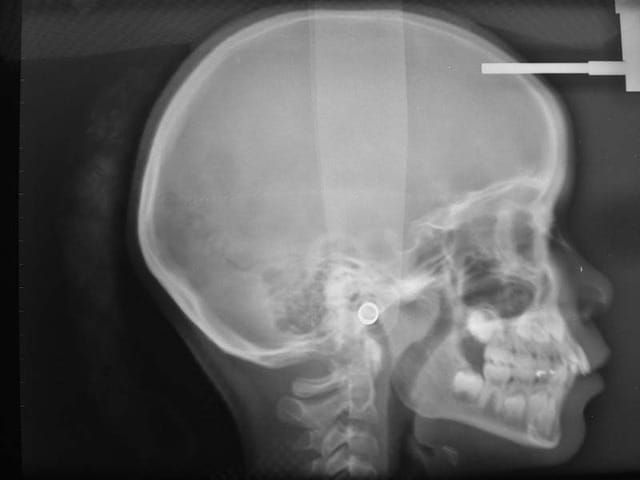

Avant TTT.

à suivre Bjc.

C’est un cas que j’ai traité en deux temps, interception, période d’interruption, fin de TTT.

ce n’est pas un cas trop difficile, aussi j’ai assez peu de photos

j’ai fait une contention parce que la patiente va quitter le département, je ne veux pas la faire rentrer dans mon étude (sans contention) sans surveillance

c'est le mm. patiente

la coloration des dents est assez remarquable